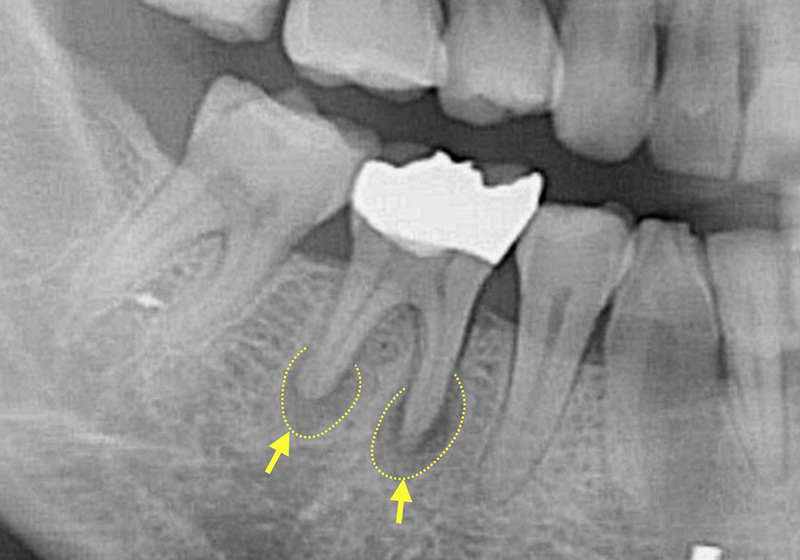

歯の内部で細菌感染が拡大すると、細菌は領土を広げるために歯の根の先から歯の外に出ていきます。

歯の根の周りには歯根膜と呼ばれる靭帯と、歯槽骨と呼ばれる骨があります。感染の広がりにより、歯根膜と歯槽骨に炎症が生じると痛みが出ます。